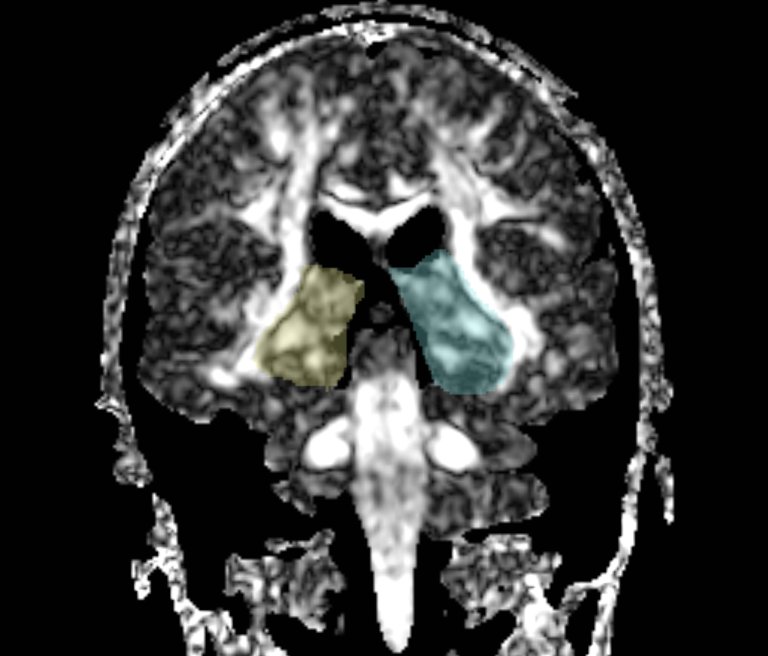

We apply fiber tractography to quantify fornix Fractional Anisotropy (FA) in schizophrenia. Two ROI method (shown in the figures) were used to extract left and right fornix in 34 chronic schizophrenia subjects and 40 matched controls, and mean FA along the entire tract was extracted separately for the left and the right sides and compared between groups. Preliminary data indicate bilateral decreased FA in the fornix of schizophrenics.